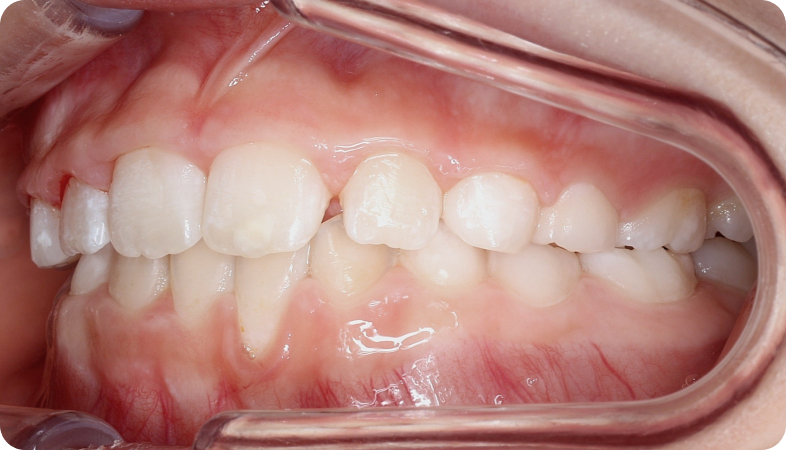

Cas cliniques